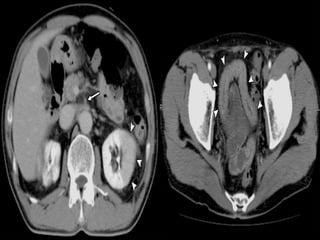

Paper thin bowel wall

White attenuation Grey attenuation

Water target sign Pneumatosis intestinalis

SMV THROMBOSIS

ARTERIAL OCLUSIVE ISCHEMIA VENOUS OCLUSIVE ISCHEMIA

SMA THROMBOSIS SMV THROMBOSIS

NO /SUBTLE BOWEL ENHANCEMENT HYPO/HYPERDENSE BOWEL WALL

THINNED BOWEL WALL (PAPER THIN

BOWEL )

SIGNIFICANT BOWEL WALL

THICKENING

NO MUCOSAL ENHANCEMENT MUCOSAL ENHANCEMENT

BOWEL LOOP DILATATION ONLY AFTER

INFARCTION

DILATED BOWEL LOOPS WITHOUT

LATE STAGES –MESENTERIC FAT

STRANDING,EDEMA/HEMORRHAGES

MARKED FAT STRANDING AND

HEMORRHAGE